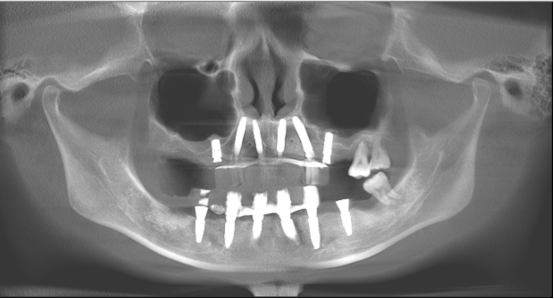

影像学检查

· 缺牙区骨量尚可,余留牙骨吸收至根尖1/3 。

· 双侧髁突骨皮质连续。

· 头影测量分析,临床诊断为:上颌前突,骨性二类错合畸形,上下中切牙及上下唇前突。

· 根据患者诉求、面型、剩余骨量、余留牙状况,拟拔除全部余留牙行全口种植固定修复。

· 上下颌计划各植入六颗straumann钛锆种植体行即刻种植即刻修复。

· 上下各计划植入6颗种植体。其中14、24种植体倾斜植入,15、25经牙槽嵴顶上颌窦提升植骨,其余牙位无需植骨。

种植体位置设计,可见上前牙唇侧骨量过丰满,需适量去骨。同时上下颌均需要截骨处理。

· 术后CBCT检查可见种植体植入位置佳,与术前设计一致。

· 修复体戴入后髁突位于关节窝内的适中位置。

· 植入精度分析,误差较小。

· X线片显示,种植体周骨稳定性、关节髁突位置评估均无异常。